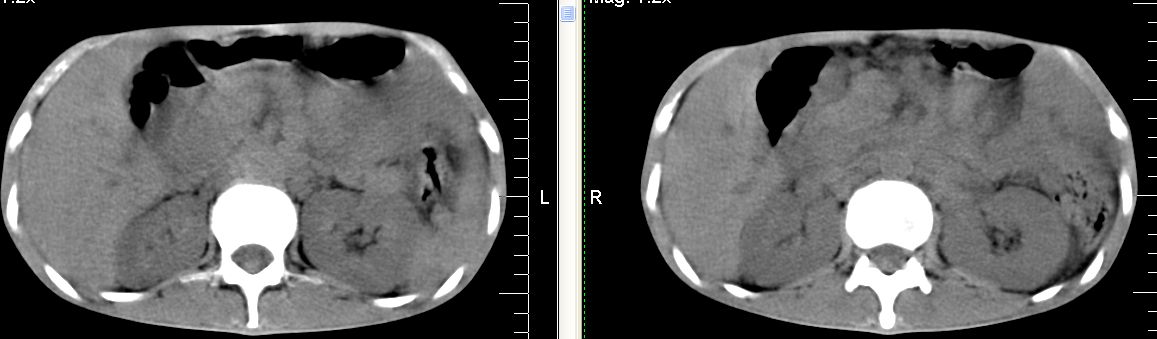

脾脏多发低密度灶,肠系膜及腹膜后见多发大小不等结节状影,右结肠旁沟见低密度影,结合病史考虑:脾结核,肠系膜及腹膜后淋巴结结核,少量腹水。

右侧结肠亦可见病变,腹膜后可见多发增大的淋巴结影,脾脏内示多个低密度结节灶,结合病史考虑结核性病变。

脾脏多发低密度灶,左侧肾上腺见块状病灶,密度不均,盲肠升结肠肠壁明显增厚,左下腹似可见肠壁增厚,肠系膜及腹膜后见多发大小不等结节状影,右结肠旁沟见低密度影,1淋巴瘤可能大,2结合病史考虑:脾结核,左侧肾上腺结核,肠系膜及腹膜后淋巴结结核,少量腹水待除外,

考虑脾结核及腹腔结核感染,阑尾区结核脓肿不排除